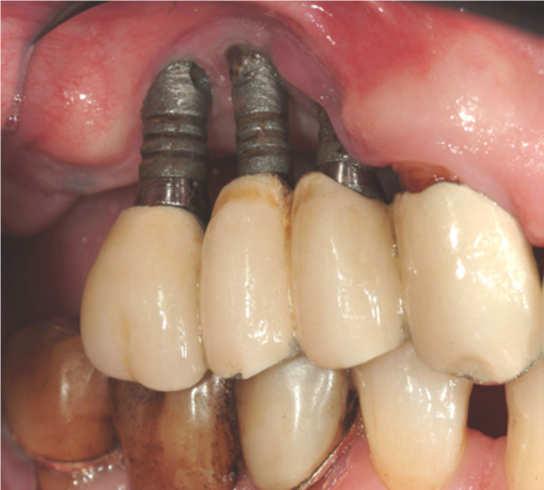

Peri-implantitis

Peri-implantitis is a dental term used to describe the destructive inflammatory process affecting the soft and hard tissues surrounding dental implants. The array of periodontal pathogens found around failing implants (those affected by peri-implantitis) are very similar to those found in association with various forms of periodontal disease.